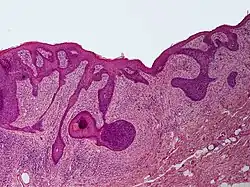

Perifollicular fibroma is a cutaneous condition, a benign tumor usually skin colored, most often affecting the face and upper trunk.[1]: 674 [2]